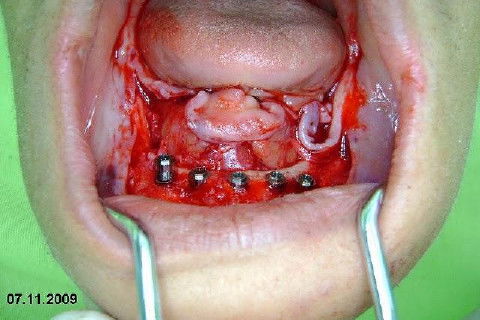

Protocolo Inferior com 5 Implantes - Parte I - Planejamento + Cirurgia

Apesar da boa adaptação e estética satisfatória, a principal queixa da paciente era a instabilidade da prótese inferior, como sempre ocorre nestes casos...atrofia do rebordo alveolar e perda da função mastigatória.